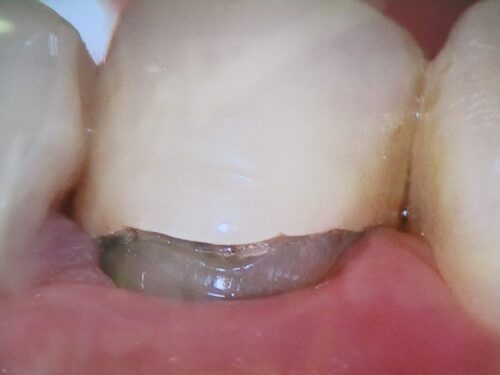

次は保険のプラスチック詰め物です。

段差があり、汚れが付着しています。隣の歯をよく見て下さい。丸みがあったはずが、削られてしまい、平面になってしまっています。